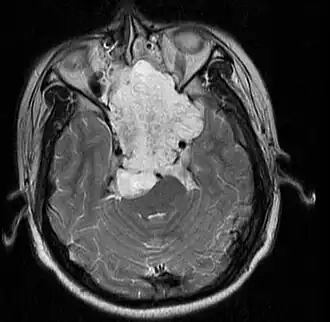

Imagen de RMN de un cordoma en un varón de 17 años, vista axial. | ||

Los cordomas pueden originarse en los huesos de la base del cráneo y en cualquier lugar del recorrido de la columna vertebral. Las localizaciones más frecuentes son el clivus y el sacro.[2]